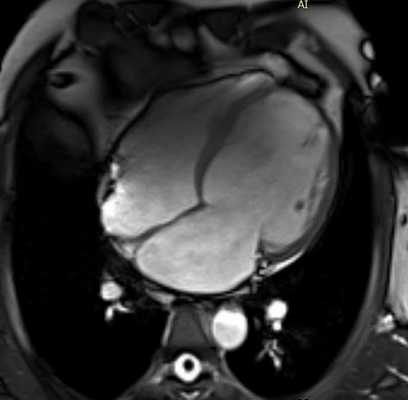

- кардиомиопатии (аритмогенная дисплазия правого желудочка, дилатационная кардиомиопатия, гипертрофическая кардиомиопатия, синдром некомпактного миокарда). Под кардиомиопатиями понимают первичные заболевания миокарда после исключения клапанных, перикардиальных и коронарных болезней. МРТ помогает разграничить ишемическую и неишемическую дилатационную кардиомиопатию. МРТ является инструментом для визуализации редких расположений гипертрофии: в правом желудочке, в апикальном сегменте левого желудочка. МРТ является одним из главных методов в выявлении аритмогенной дисплазии правого желудочка (АДПЖ). Главные признаки АДПЖ на МРТ: локальное нарушение сократимости ПЖ, дилатация ПЖ, усиление трабекулярности ПЖ и отсроченное контрастирование миокарда ПЖ

Рисунок 3. МРТ. Четырехкамерное сечение сердца. Апикальная гипертрофия миокарда левого желудочка.

Рисунок 4. МРТ. Четырехкамерное сечение сердца. Миокардит, субэпикардиальное и интрамиокардиальное накопление контрастного препарата.